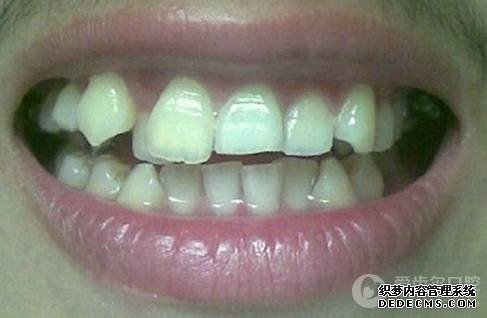

临床诊断:通过3D数字化全景机的拍片检查,患者上下牙排列拥挤,前牙受挤压向内歪斜,咬合关系异常,唇形尚可,颞下颌关节检查未见异常,无蛀牙、牙周疾病症状。经过和患者商量,选定自锁托槽矫正方案,调整牙间隙,恢复牙齿的正常排列,实现正常的咬合关系。

矫正前旧照

矫正前照片